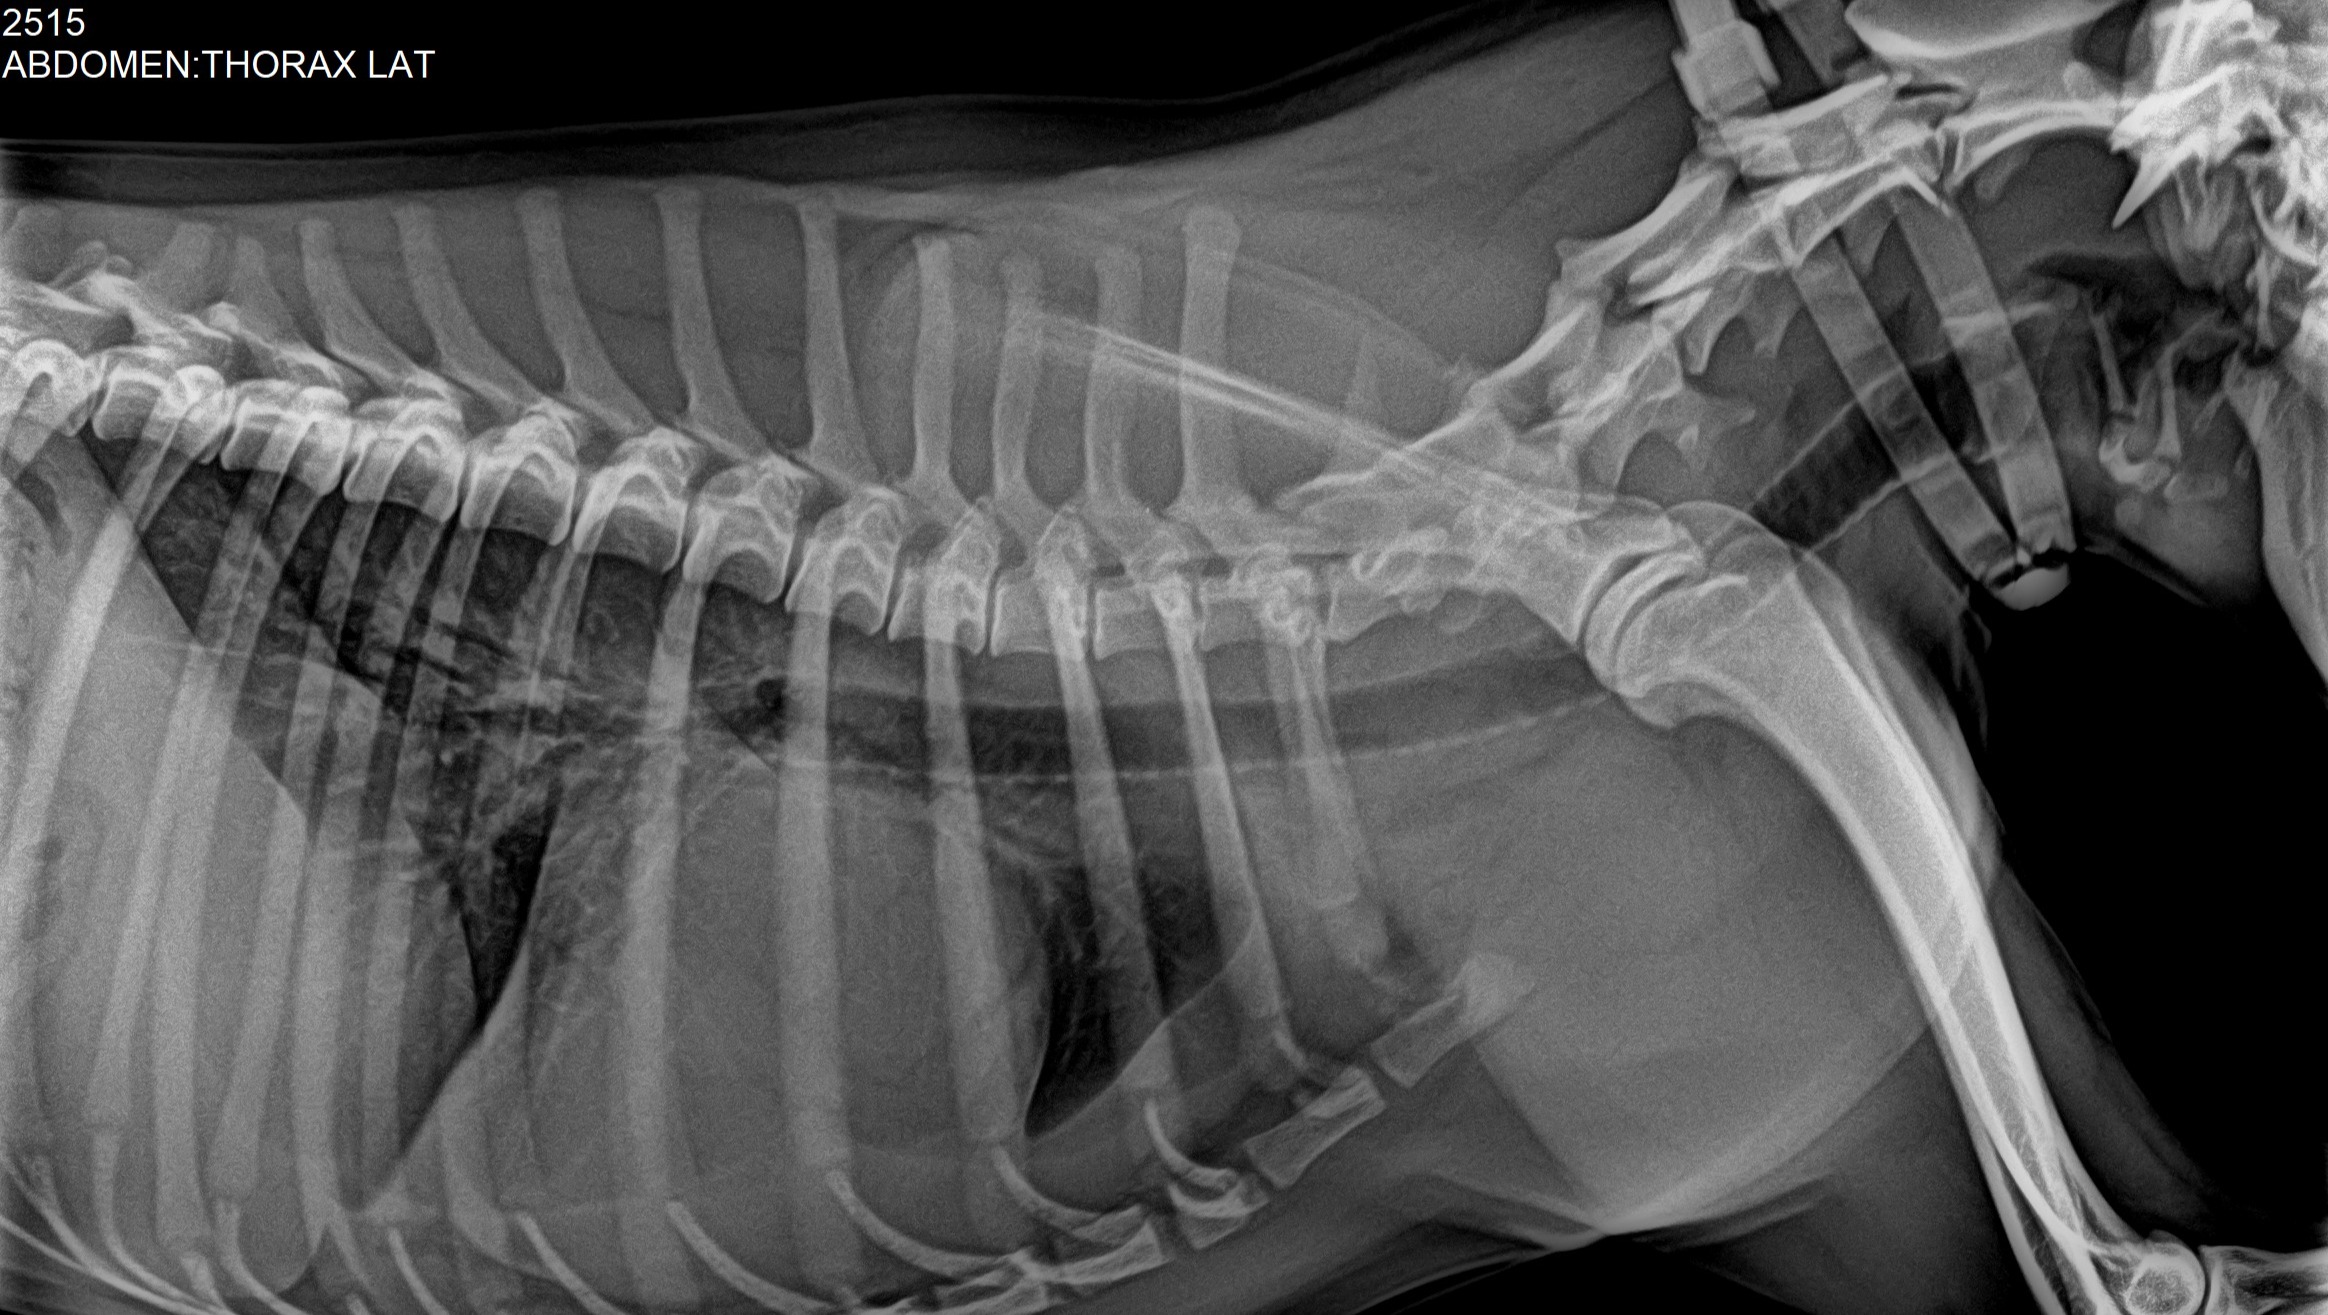

Hola, mi cachorro Pakito sufre de una mal formación en el corazón, tiene displasia en la válvula tricúspide. Explicándolo mal resumido sus válvulas no funcionan adecuadamente y no expulsa la sangre del corazón como debería por lo que el corazón agranda y agranda hasta que colapsa.